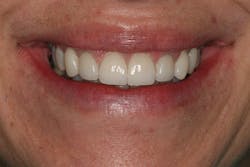

Careful technique and accurate records provided the lab with the information required to provide a result that replicated the contours of the provisional restorations. The seat appointment proceeded smoothly with no adjustments (figures 16, 17).

Conclusion

This case clearly illustrates the benefit of proper tissue management and tooth contour. Modification of tissue support and tissue training were the key elements in developing natural implant results that took this patient from being dissatisfied to loving her smile. The additional time invested in planning and manipulating soft tissues was critical to the long-term success of this implant case (figures 18, 19).